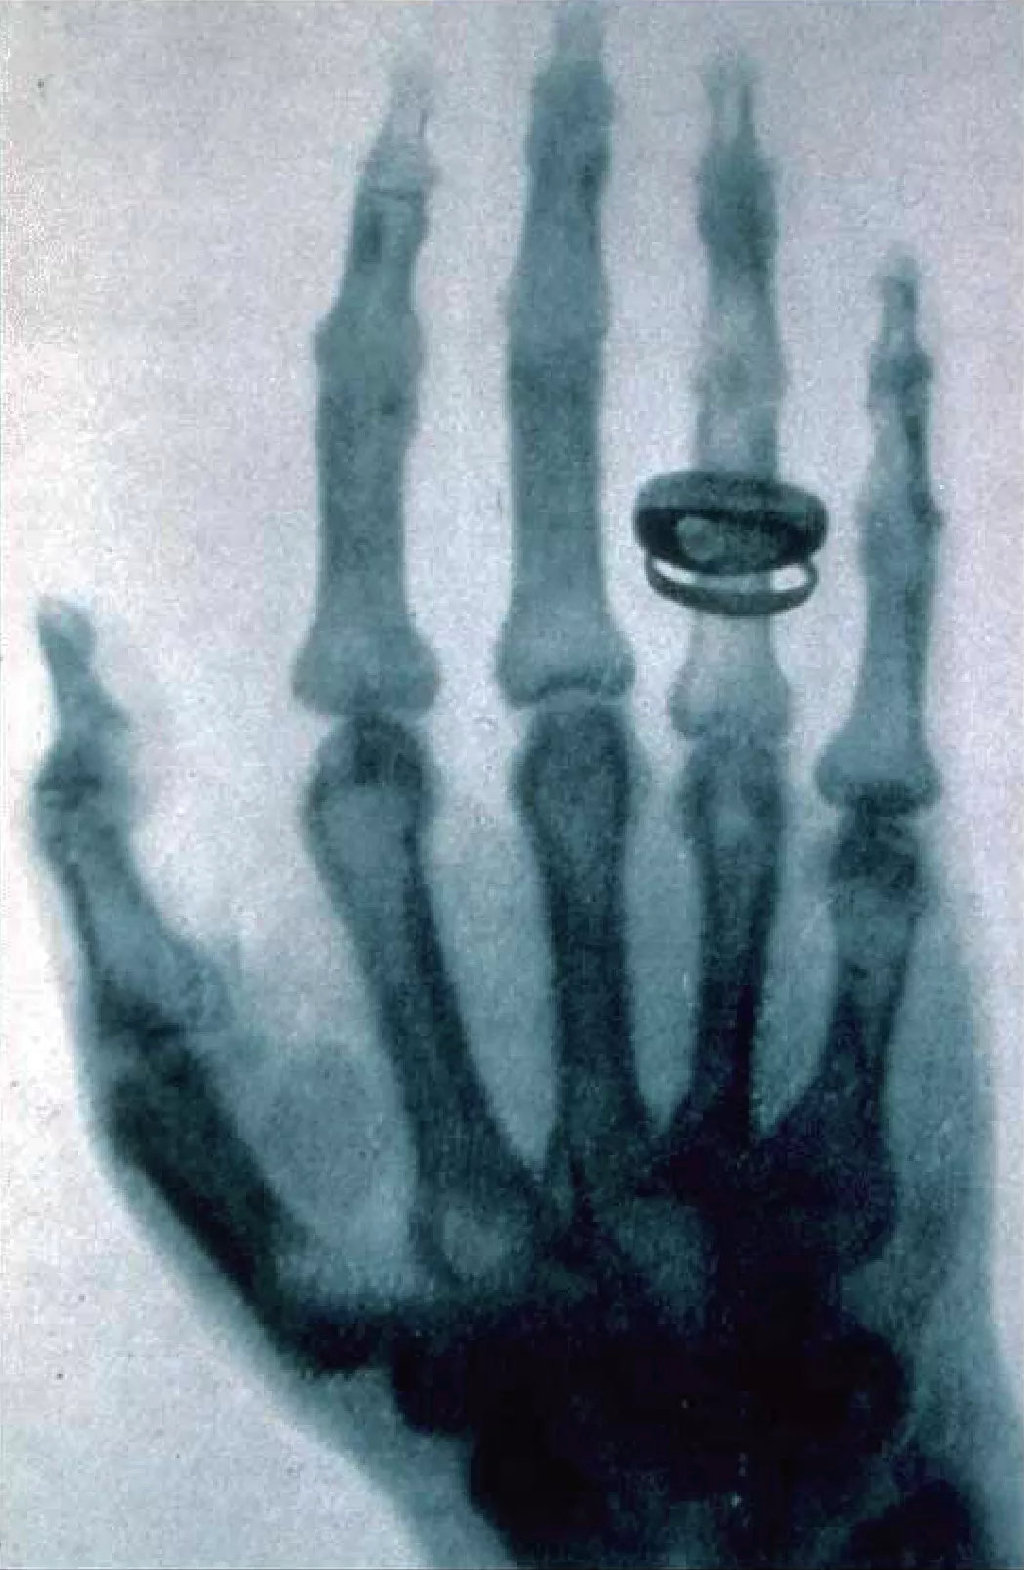

伦琴妻子手指x光照片